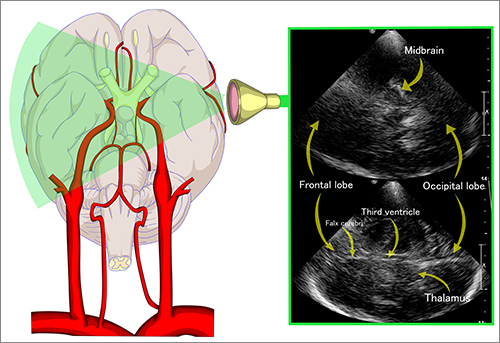

Transcranial dopler sonography

While transcranial Doppler is the only noninvasive tool supported by guidelines to detect angiographic vasospasm, it is limited by poor sensitivity and interrater reliability, and lack of temporal bone windows in some adults.